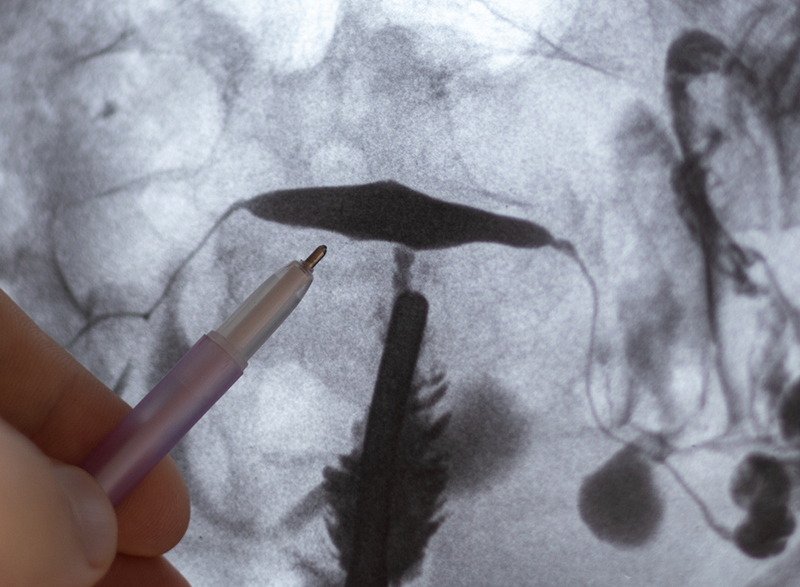

Stage 3: Diagnostic Laparoscopy

Diagnostic laparoscopy is an accurate tool that truly facilitates endometriosis diagnosis and treatment. It enables specialists to remove and examine tissue samples from inside the abdomen through a very small opening. Once endometriosis diagnosis is confirmed, it is staged, and removed from the pelvis. This surgery provides an answer and treatment together.